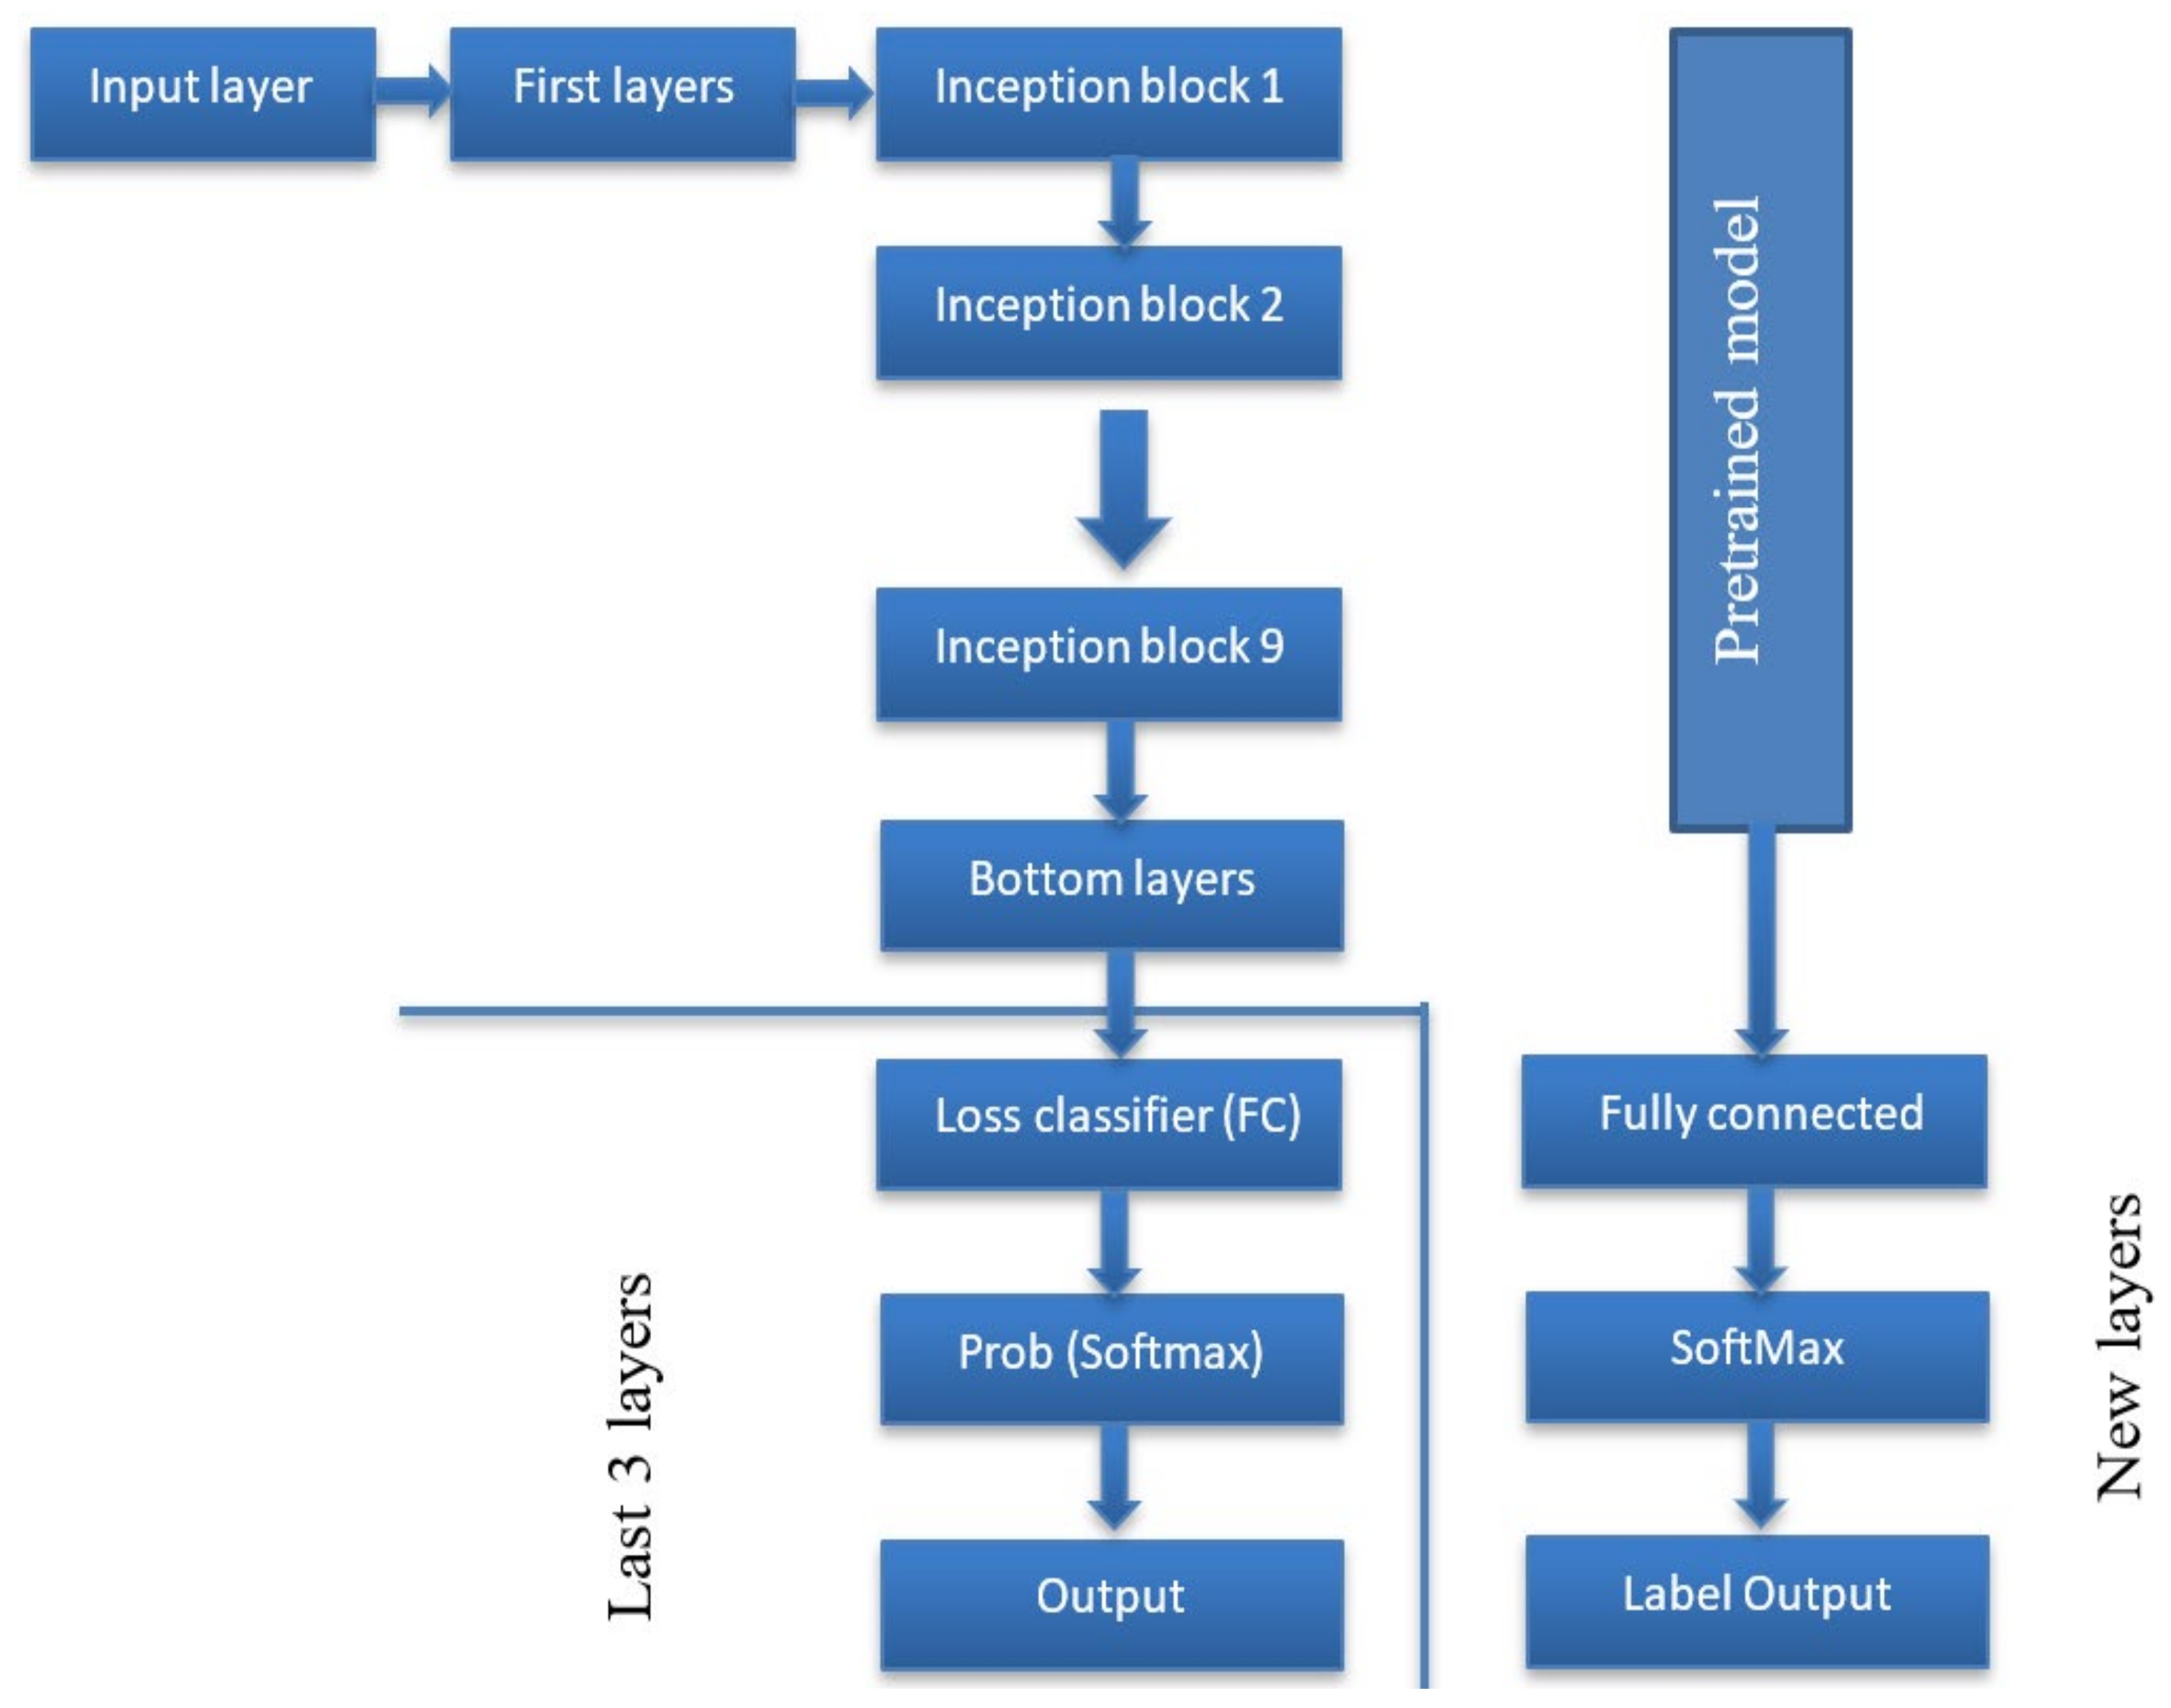

2.2. The Proposed Algorithm

2.2.2. Feature Extraction

2.2.3. Classification

- Szegedy, C.; Liu, W.; Jia, Y.; Sermanet, P.; Reed, S.; Anguelov, D.; Erhan, D.; Vanhoucke, V.; Rabinovich, A. Going deeper with convolutions. In Proceedings of the IEEE Conference on Computer Vision and Pattern Recognition (CVPR), Boston, MA, USA, 7–12 June 2015; pp. 1–9. [Google Scholar]